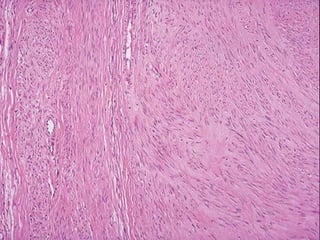

Fibromatosis Profunda

 Musculo aponeurótica

 Entre tumores fibrosos benignos y fibrosarcoma

 Masas infiltrantes grandes

 Crecimiento rápido

 Bien diferenciado

 Reaparecen post resección incompleta

 No predilección de edad ( adolescencia y 4°

década)

 Profunda (músculo aponeurótica ; tumor